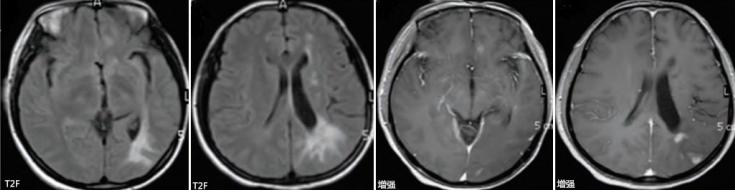

Sturge-Weber综合征

Sturge-Weber综合征是一种以皮肤、脑、眼部损害为临床特征的静脉微血管系统的先天性病变。

临床表现为面部“葡萄酒”色血管瘤、青光眼、癫痫发作、偏瘫及智力下降等。

影像表现为皮质不同程度的钙化、脑萎缩、脑回样脑膜强化及深静脉增多、扩张。